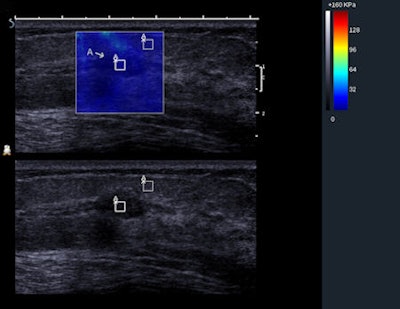

BE1 SWE of a heterogeneous lesion that proved to be malignant. This impalpable lesion was found at mammography in a 66-year-old patient. On B-mode, the investigator scored the lesion as BI-RADS 4a. The heterogeneous pattern on the elasticity map confirmed the level of suspicion. The pathological outcome was a mixture of invasive and in situ ductal carcinoma. Image courtesy of Dr. Fritz KW Schäfer, University Hospital, Schleswig-Holstein in Kiel, Germany.The heterogeneity of the SWE stiffness was moderately predictive of malignancy in the full set of masses with 70.6% of heterogeneous masses malignant, compared with 4.3% of homogenous masses in a population with 30.8% prevalence of malignancy.